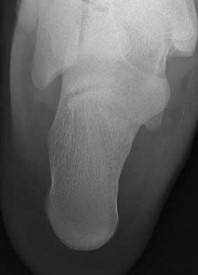

QUESTION 4

Figures 4a through 4j

1

Normal foot

Figures 4a through 4j do not show any signs of a coalition.